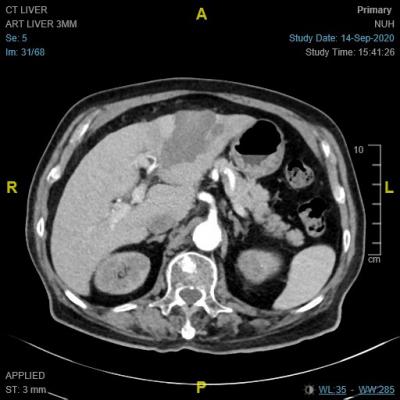

当然,对病人来说,在肝脏里发现硬块都不会是好消息。肾科的同事迅速联络我,看看是否可以尽早会诊。如果要通过正常管道安排门诊,可能须等上两周至一个月。面对患有肿瘤的病人,我们通常都会尽快安排以便提早治疗。由于超声波只是初步检查,他必须做更详细的扫描。我们马上安排了电脑断层扫描,但是老翁的慢性肾病必须加以关注,他入院吊了点滴,做了扫描。入院时,老翁有一女士陪伴。切问之下,女士是老翁友人,对他的病情非常了解,也对他照顾有加。扫描结果确诊了,老翁患有原发性肝癌(图A)。面对确诊结果,两人非常坦然,询问了治疗的选择。

上星期,病人及友人来复诊,他行动自如,声音响亮,中气十足。我们也安排了扫描检查肝肿瘤治疗后的成果,肿瘤已经完全消灭(图B),可喜可贺!病人的友人非常激动,走出门诊室后,又再次折返鞠躬道谢!真令人感动。